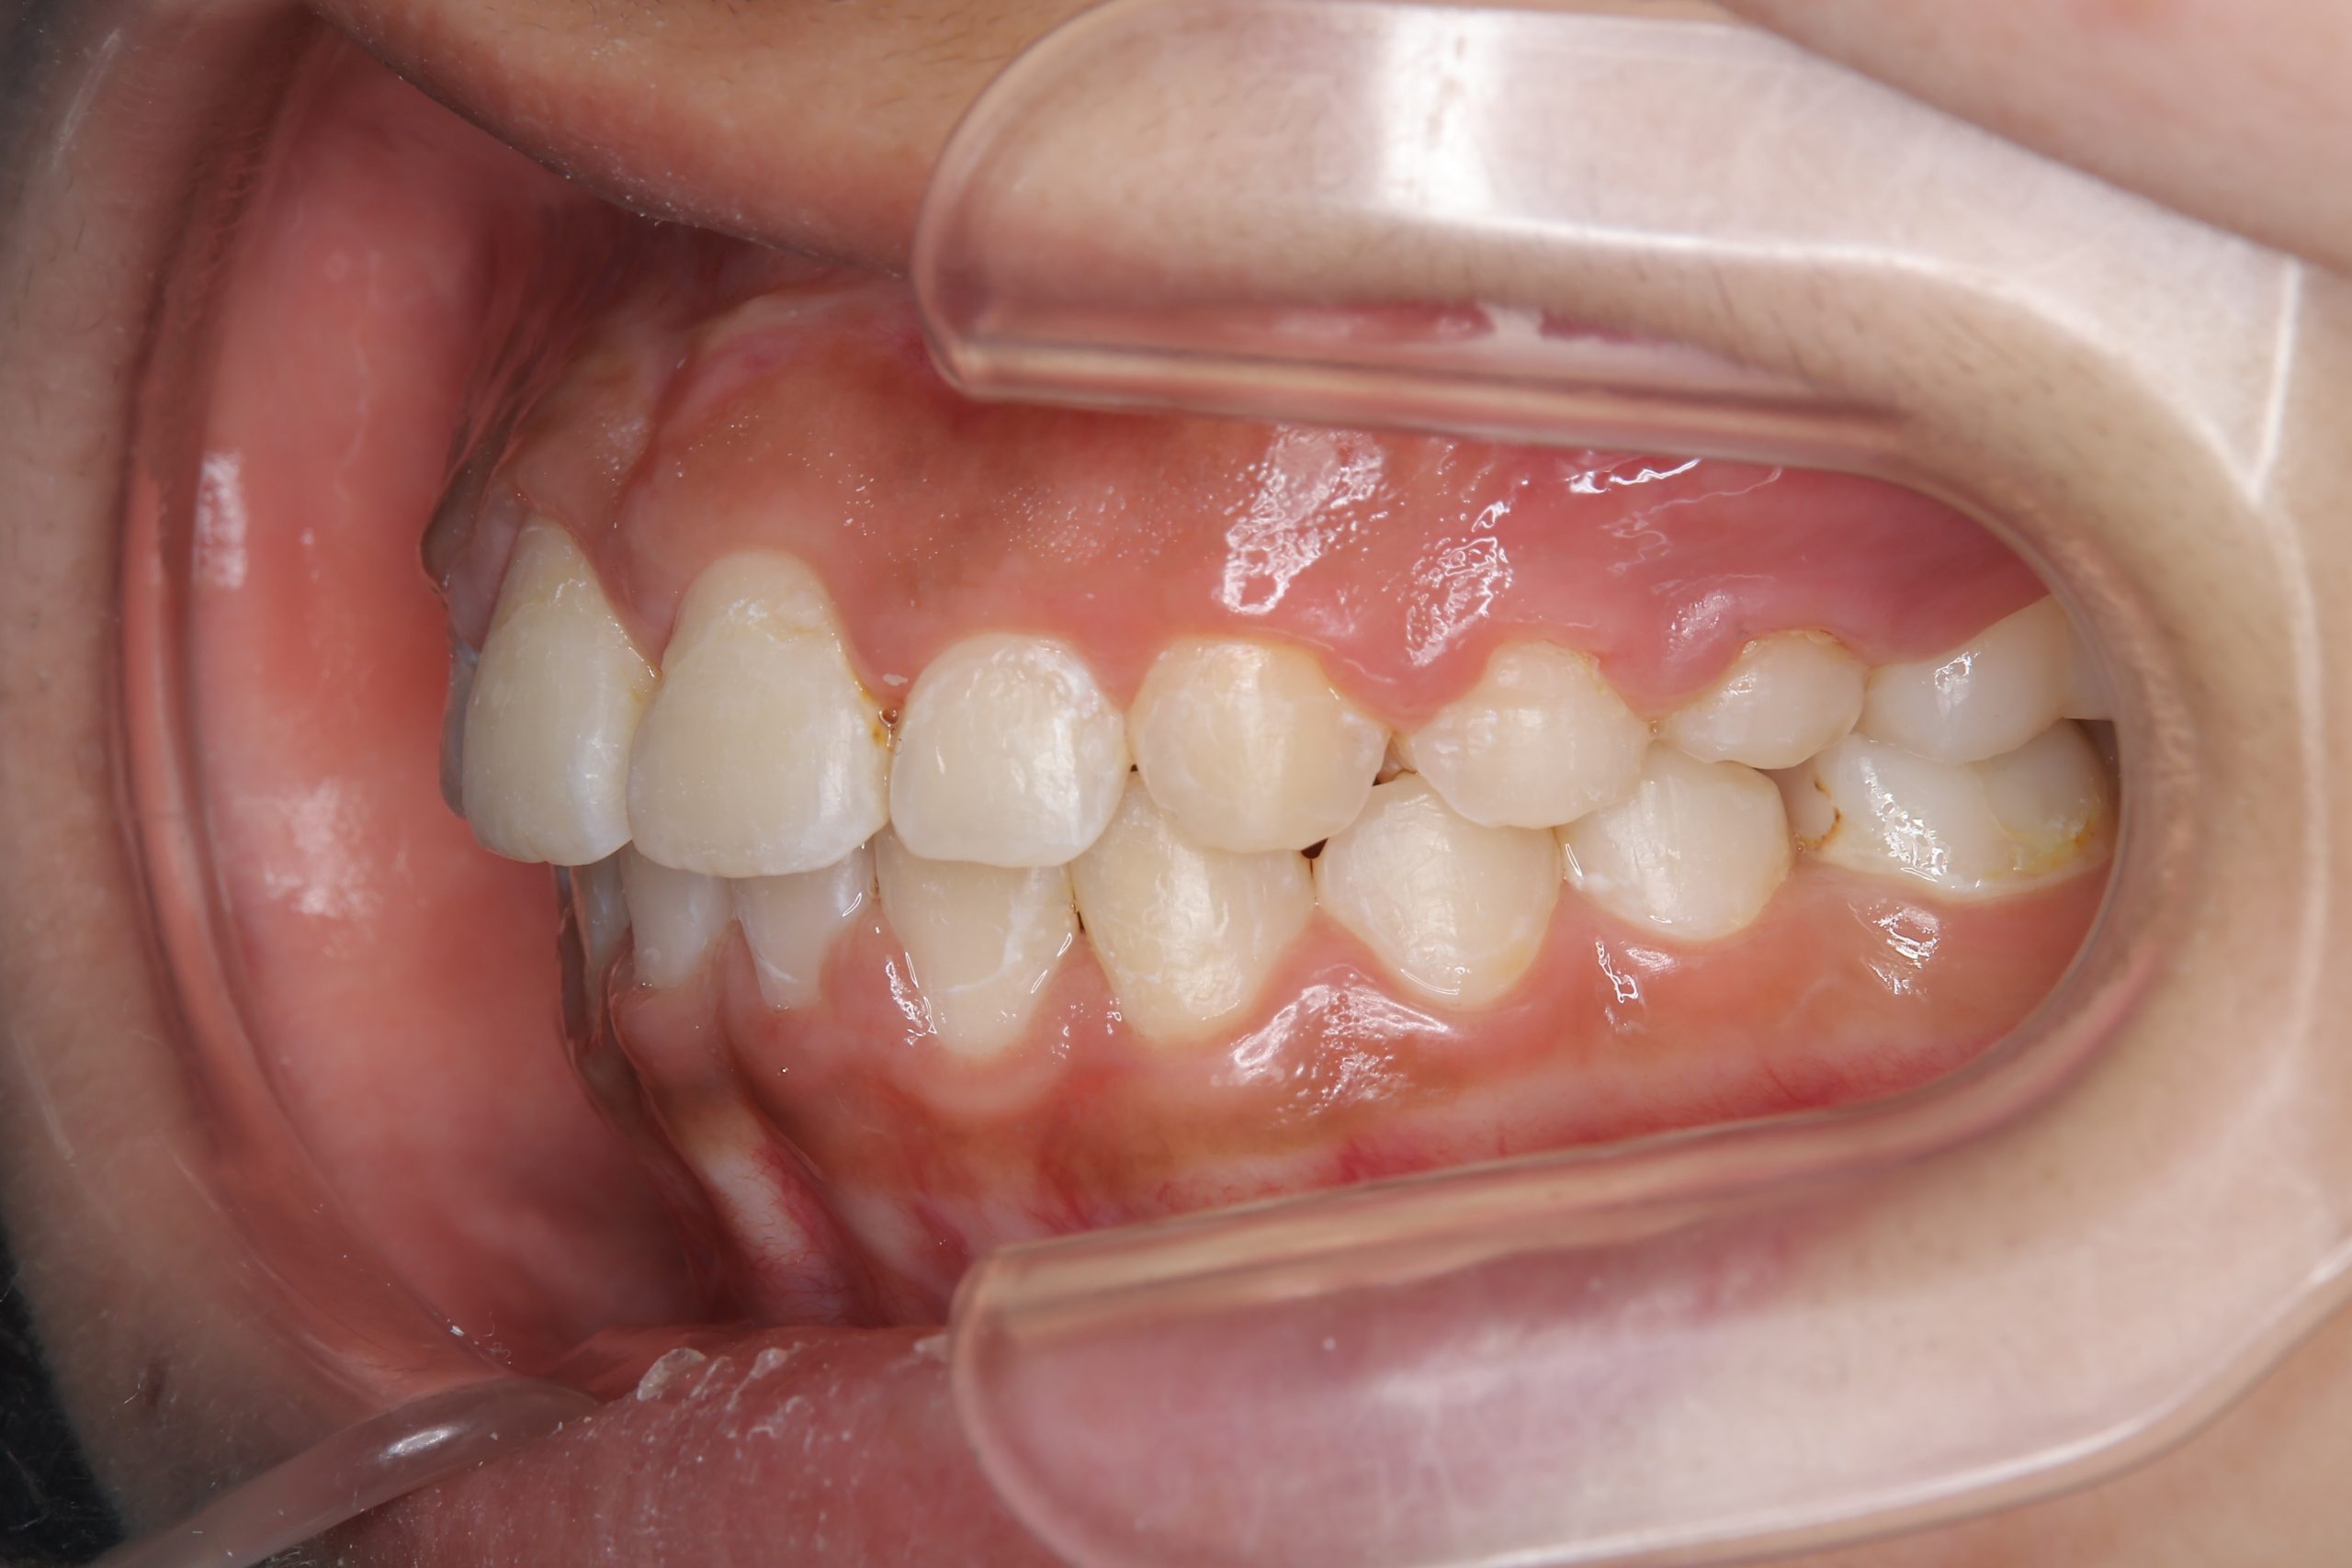

ビフォー

全顎ワイヤー矯正 症例_474

アフター

主訴 歯並びがガタガタで前歯が出ている

施術内容 小児矯正1期治療

治癒期間 1年5か月間

費用 1,020,800円(税込)